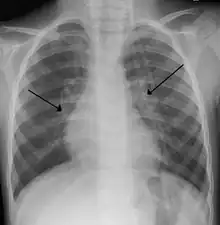

| An X-ray of a child with RSV showing the typical bilateral perihilar fullness of bronchiolitis. | |

The diagnosis is typically made by clinical examination. Chest X-ray is sometimes useful to exclude bacterial pneumonia, but not indicated in routine cases.[17] Chest x-ray may also be useful in people with impending respiratory failure.[18] Additional testing such as blood cultures, complete blood count, and electrolyte analyses are not recommended for routine use although may be useful in children with multiple comorbidities or signs of sepsis or pneumonia.[7][18]